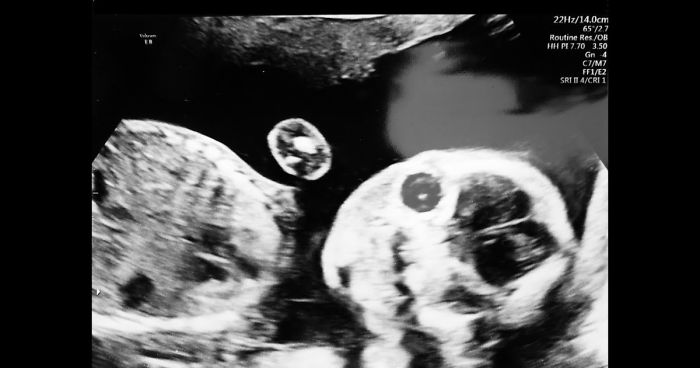

The day everything changed…

14th February 2018. A Valentine’s day present like no other!